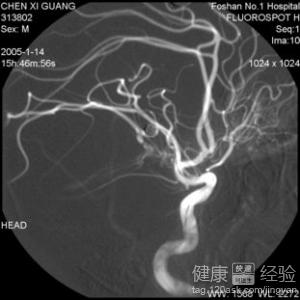

3最後,對於腦血管失語症來說,在腦血管病中,最常用的是運動性失語,其次是感覺性失語。如果兩者並存者叫做混合性失語。命名性失語的中樞,在優勢半球颞葉後部和頂葉上部,當這個部位受損時,就會發生上述情況的失語。